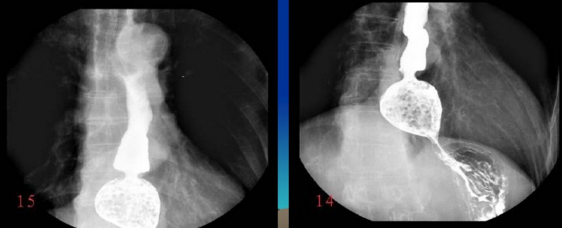

很多人沒有接觸到數(shù)字胃腸一體機(jī),可能對(duì)它還比較陌生。其實(shí)它是一款多功能數(shù)字造影胃腸機(jī),功能強(qiáng)大,操作便捷,可以真正實(shí)現(xiàn)數(shù)字化攝影,以及無膠片化管理,配置先進(jìn)的工作站,可以保證其圖像畫質(zhì)。同時(shí)它在臨床上的應(yīng)用也比較的廣泛,能夠檢查多種疾病。下面,由普愛醫(yī)療小編詳細(xì)列舉一些。

2、選擇性小腸造影。

3、氣鋇雙重對(duì)比造影。